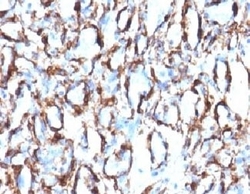

- Enhanced method

- Genetic validation

- Main image

- Experimental details

- Formalin-fixed, paraffin-embedded human angiosarcoma stained with alpha Smooth Muscle Actin antibody (ACTA2/791). This image was taken for the unmodified form of this product. Other forms have not been tested.

- Main image

- Experimental details

- Formalin-fixed, paraffin-embedded human angiosarcoma stained with alpha Smooth Muscle Actin antibody (ACTA2/791). This image was taken for the unmodified form of this product. Other forms have not been tested.

- Genetic validation

- Main image

- Experimental details

- Formalin-fixed, paraffin-embedded human angiosarcoma stained with alpha Smooth Muscle Actin antibody (ACTA2/791). This image was taken for the unmodified form of this product. Other forms have not been tested.